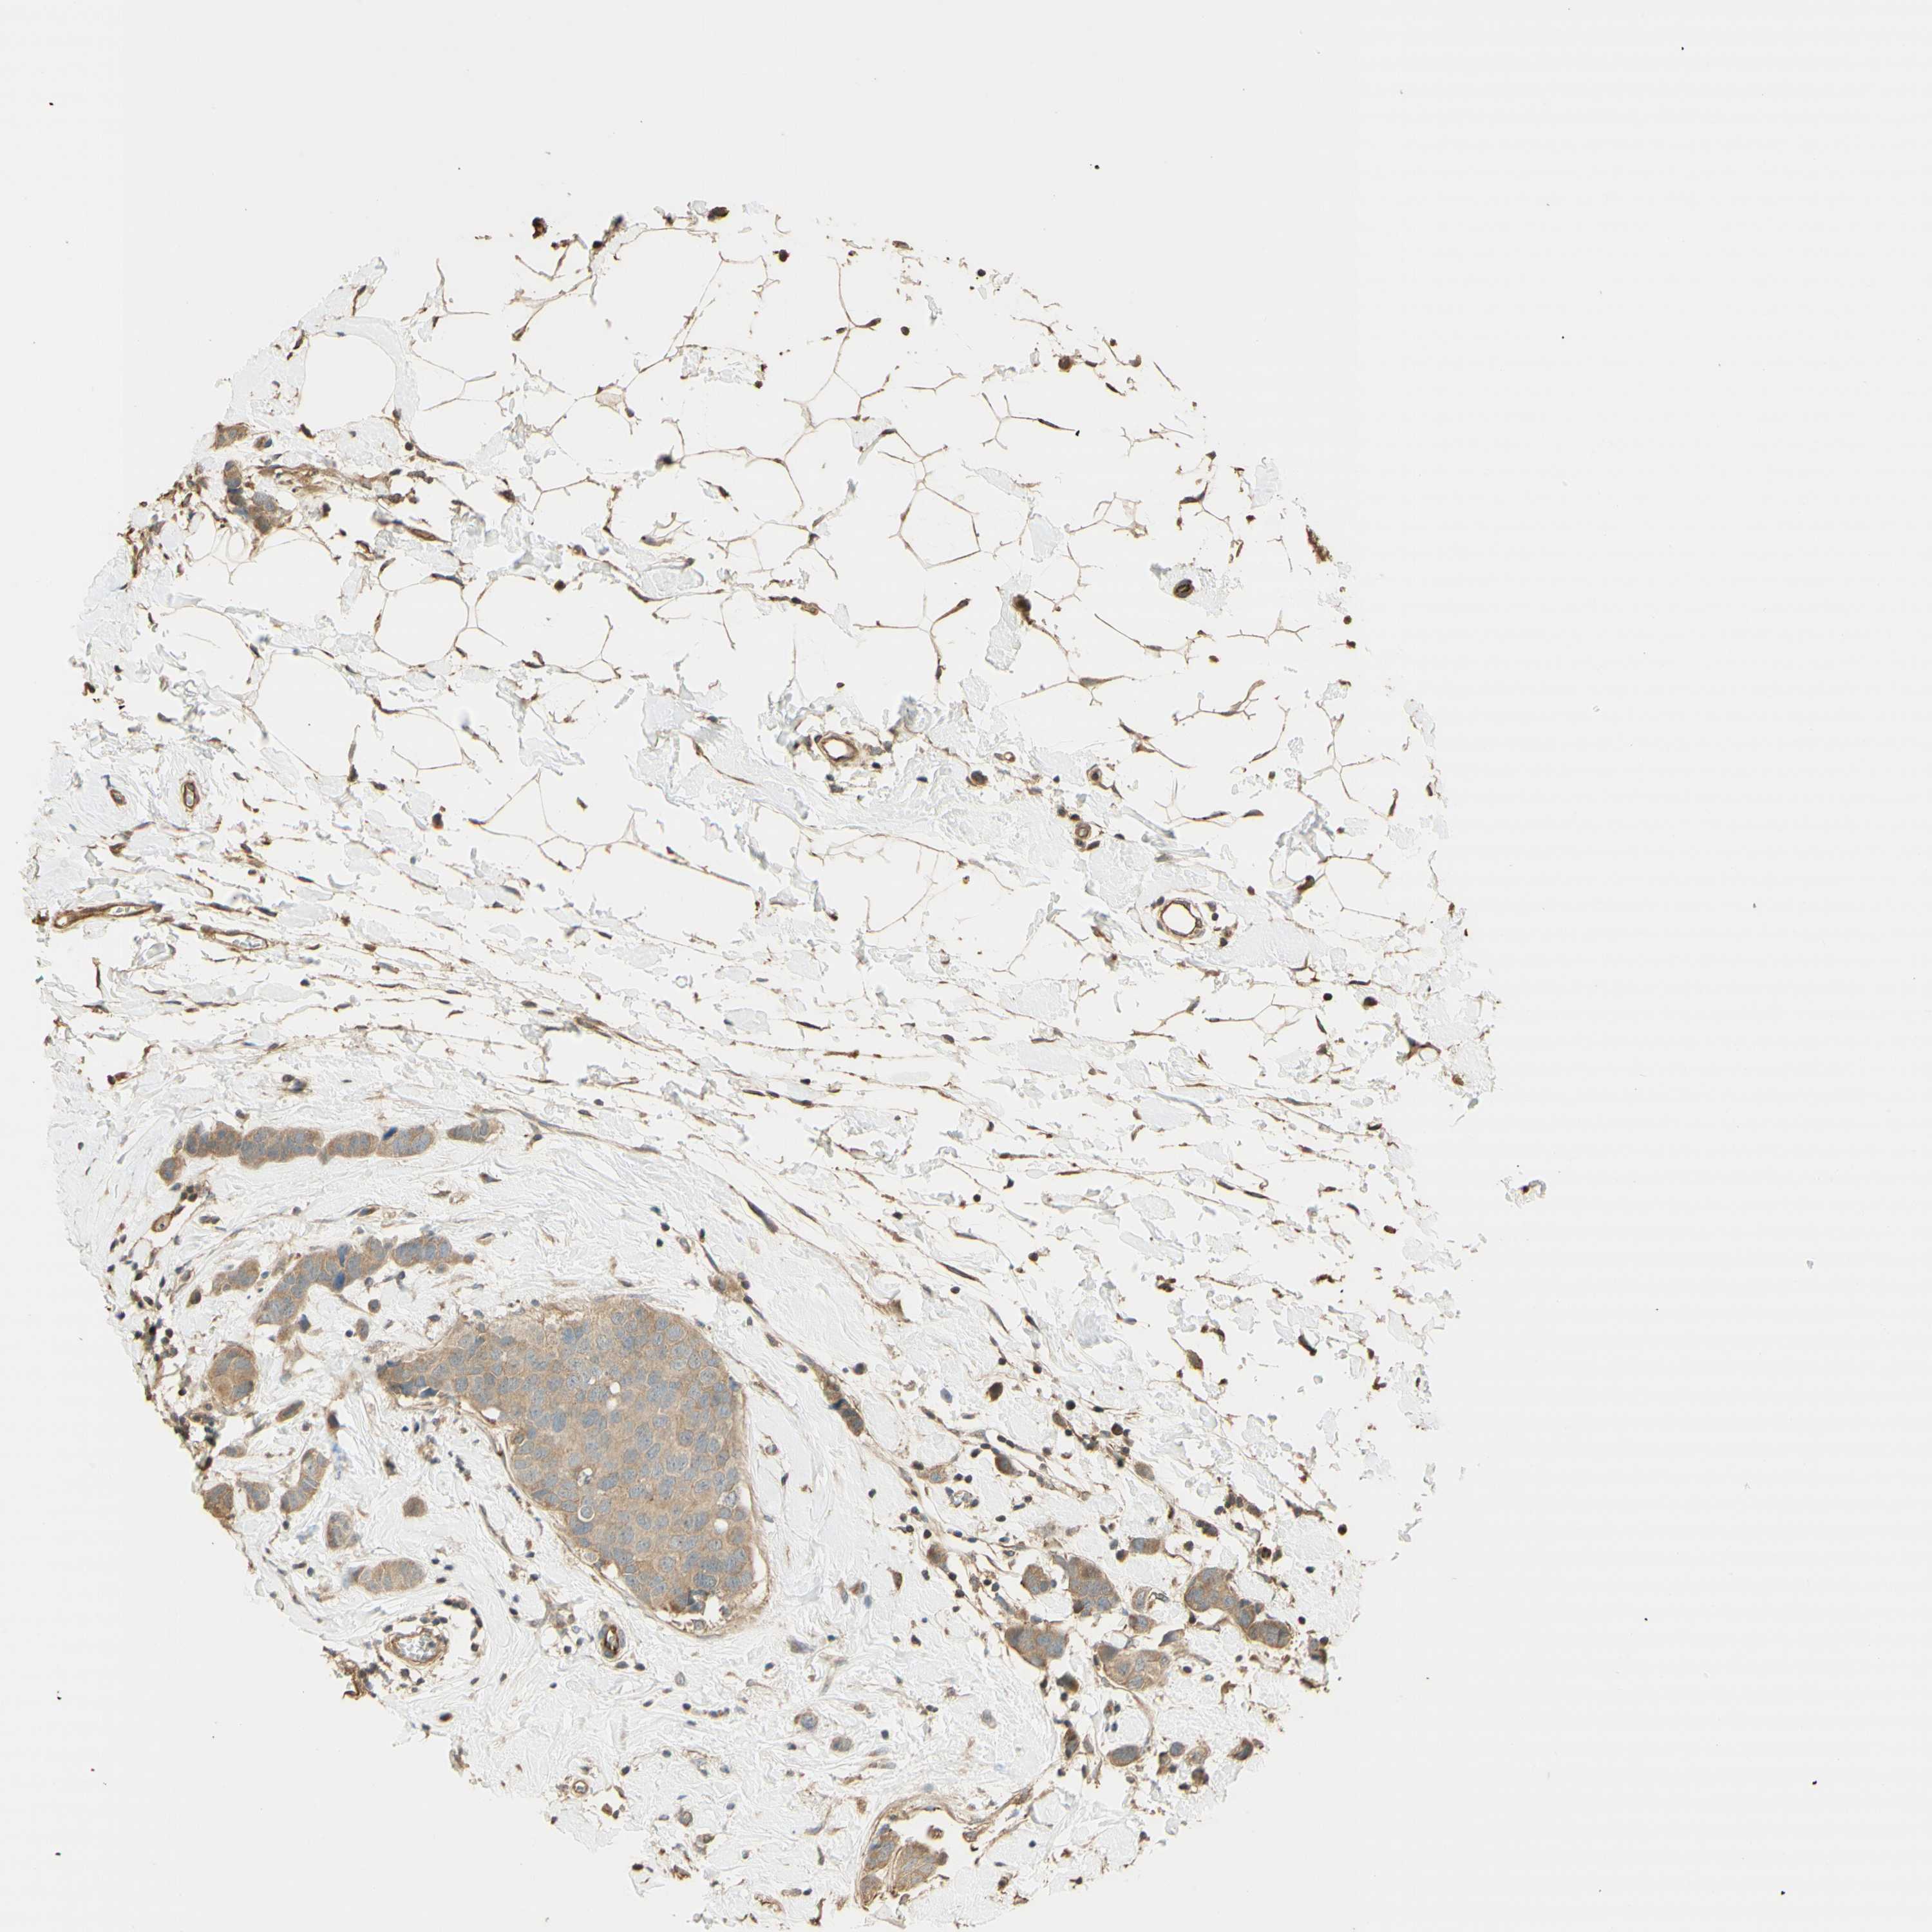

CANCER BREAST CANCER Show tissue menu

BRCA TCGA BRCA VALIDATION PROTEIN EXPRESSION

ANTIBODIES

AND

VALIDATION